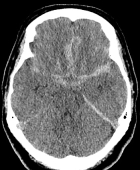

Tomografia computadorizada de um homem de 45 anos com hematoma intracerebral.

Tomografia de homem de 45 anos com hemorragia intracerebral.